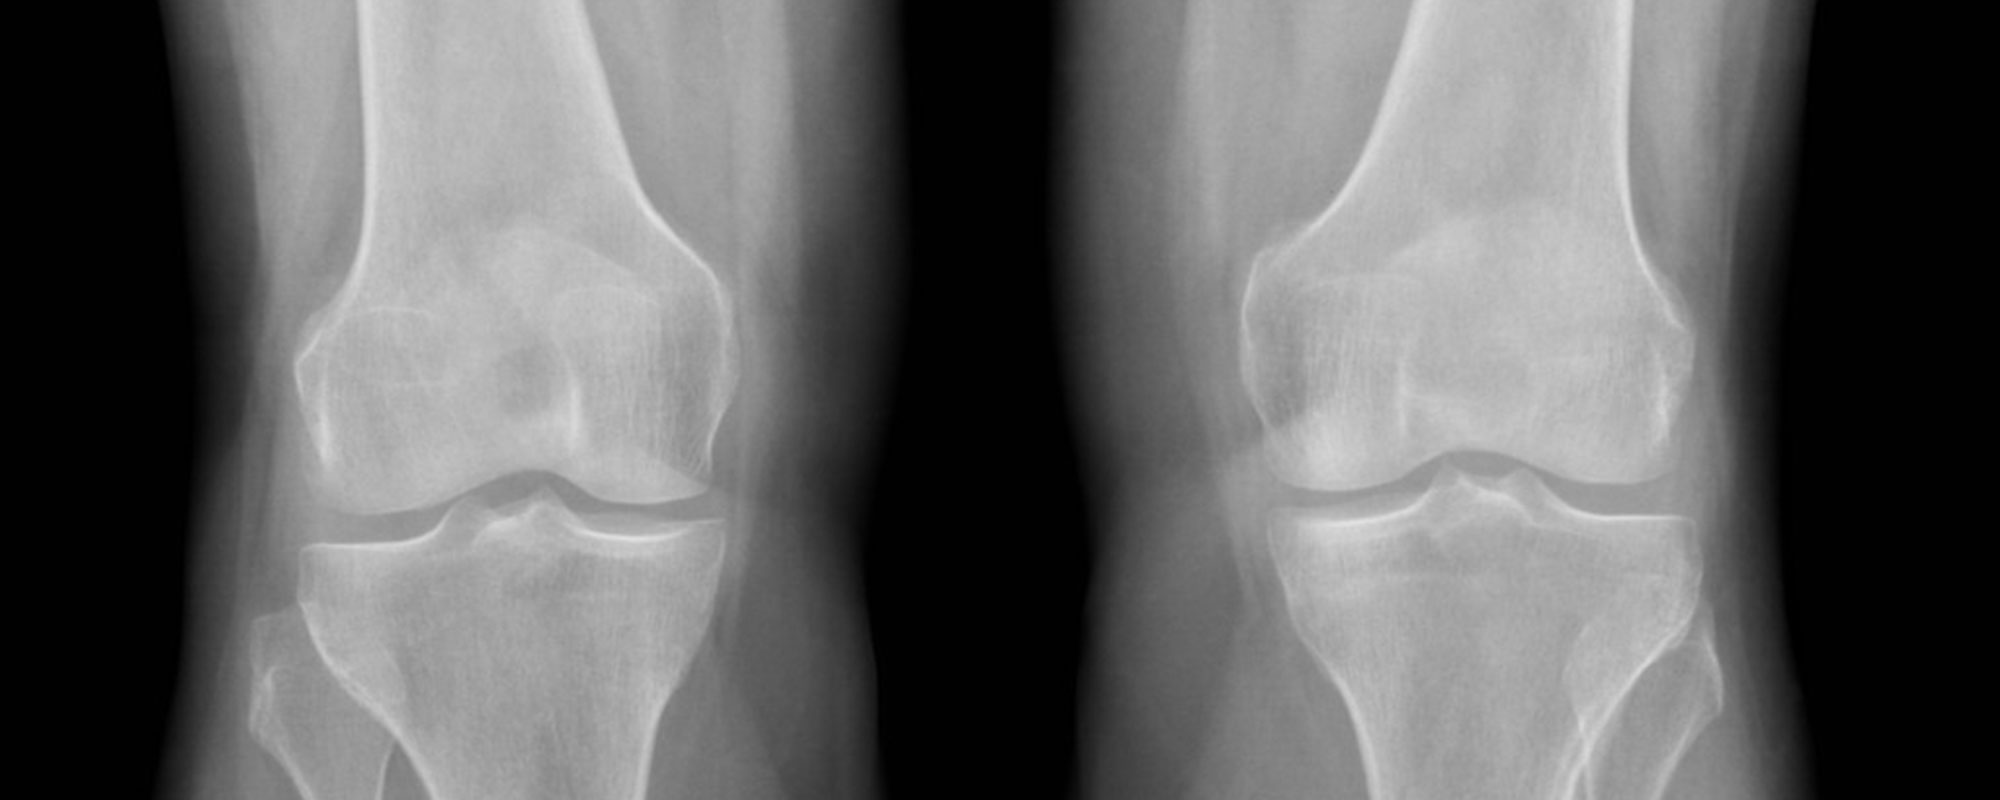

Медицинские снимки: рентген коленного сустава при остеопорозе